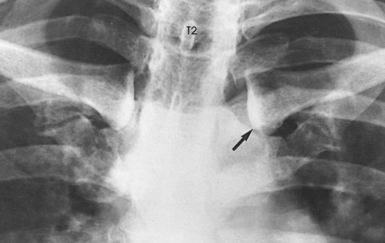

Fig. 9-26 A, PA oblique sternoclavicular joint, LAO position: Body rotation method. B, Axial view (from feet upward) of central ray position in relation to spine and sternoclavicular joint. C, PA oblique sternoclavicular joint, LAO position. The joint closest to IR is shown (arrow). CR, central ray.

• Perpendicular to the sternoclavicular joint closest to the IR. The central ray enters at the level of T2-3 (about 3 inches [7.6 cm] distal to the vertebral prominens) and 1 to 2 inches (2.5 to 5 cm) lateral from the midsagittal plane. If the central ray enters the right side, the left sternoclavicular joint is shown, and vice versa (see Fig. 9-26, B).

Structures shown: A slightly oblique image of the sternoclavicular joint is shown (see Fig. 9-26, C).